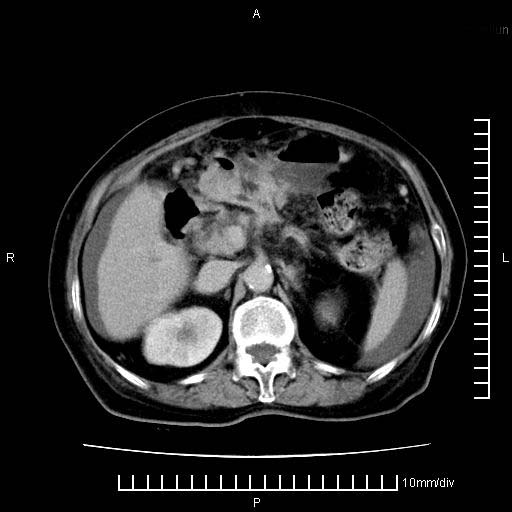

4。右肾盂囊肿。

右肾盂囊肿。

3、右肾盂囊肿。

1)考虑胰腺癌并胰腺假性囊肿形成。2)肝内低密度灶,不排除转移。3)右肾盂积水。4)腹水。5)右侧胸腔积液并右肺下叶部分膨胀不全。

考虑胰腺ca伴腹膜腔转移、肝左叶转移、右肾积水。右胸腔积液。